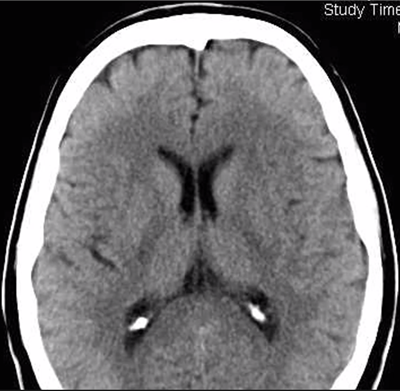

Patienten kommer in med förmodad stroke, NIH-strokeskala görs först, vilken undersökning vill du göra sen?

Vad ses på denna DT?